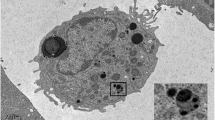

Lesions greater than 70% stenosis demonstrated significantly higher contrast-to-noise ratio (CNR) values as compared to lesions below that threshold (7.6 ± 8.31vs.2.5 ± 4.9;p < 0.001). Figure 1 demonstrates a sample where high signal enhancement at sites of lesions with greater than 70% stenosis is visible (see Fig. 1), whereas Fig. 2 shows only mild signal enhancement on Gadofosveset-enhanced CMR at sites of lesion with only minimal to mild stenosis (see Fig. 2). ROC analysis for the detection of lesions greater than 50% and greater than 70% revealed an area under the curve (AUC) of 0.667 (95% CI 0.586–0.748) and 0.774 (95% CI 0.681–0.866), respectively (see Fig. 3A). There was no difference in CNR values between segments located proximally and distally of lesions with stenosis greater than 50% (3.3 ± 2.8 vs. 2.4 ± 2.7; p = 0.18) (see Fig. 3B). However, segments located distally of lesions with greater than 70% stenosis showed significant higher signal enhancement compared to segments located proximally of these lesions (7.3 ± 8.8 vs. 2.8 ± 2.2; p = 0.02) (see Fig. 3C).

Representative images demonstrating on minimal signal enhancement at sites of non-relevant stenosis following the administration of an albumin-binding MR probe. To highlight the anatomical relationship between the uptake of the albumin-binding-MR probe (b) and morphology from the MR angiography, images were fused in a way comparable to positron emission tomography/computed tomography (a). Subsequent Invasive catheterization demonstrated only a minimal stenosis in the left arterial descending artery (LAD) (C)